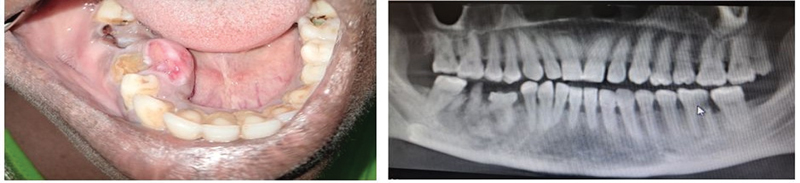

| Figure 4: Clinical and radiographic images of a 40-year-old male patient with cancer of the left lateral border of the tongue and the floor of the mouth with no known risk factors other than periodontitis.